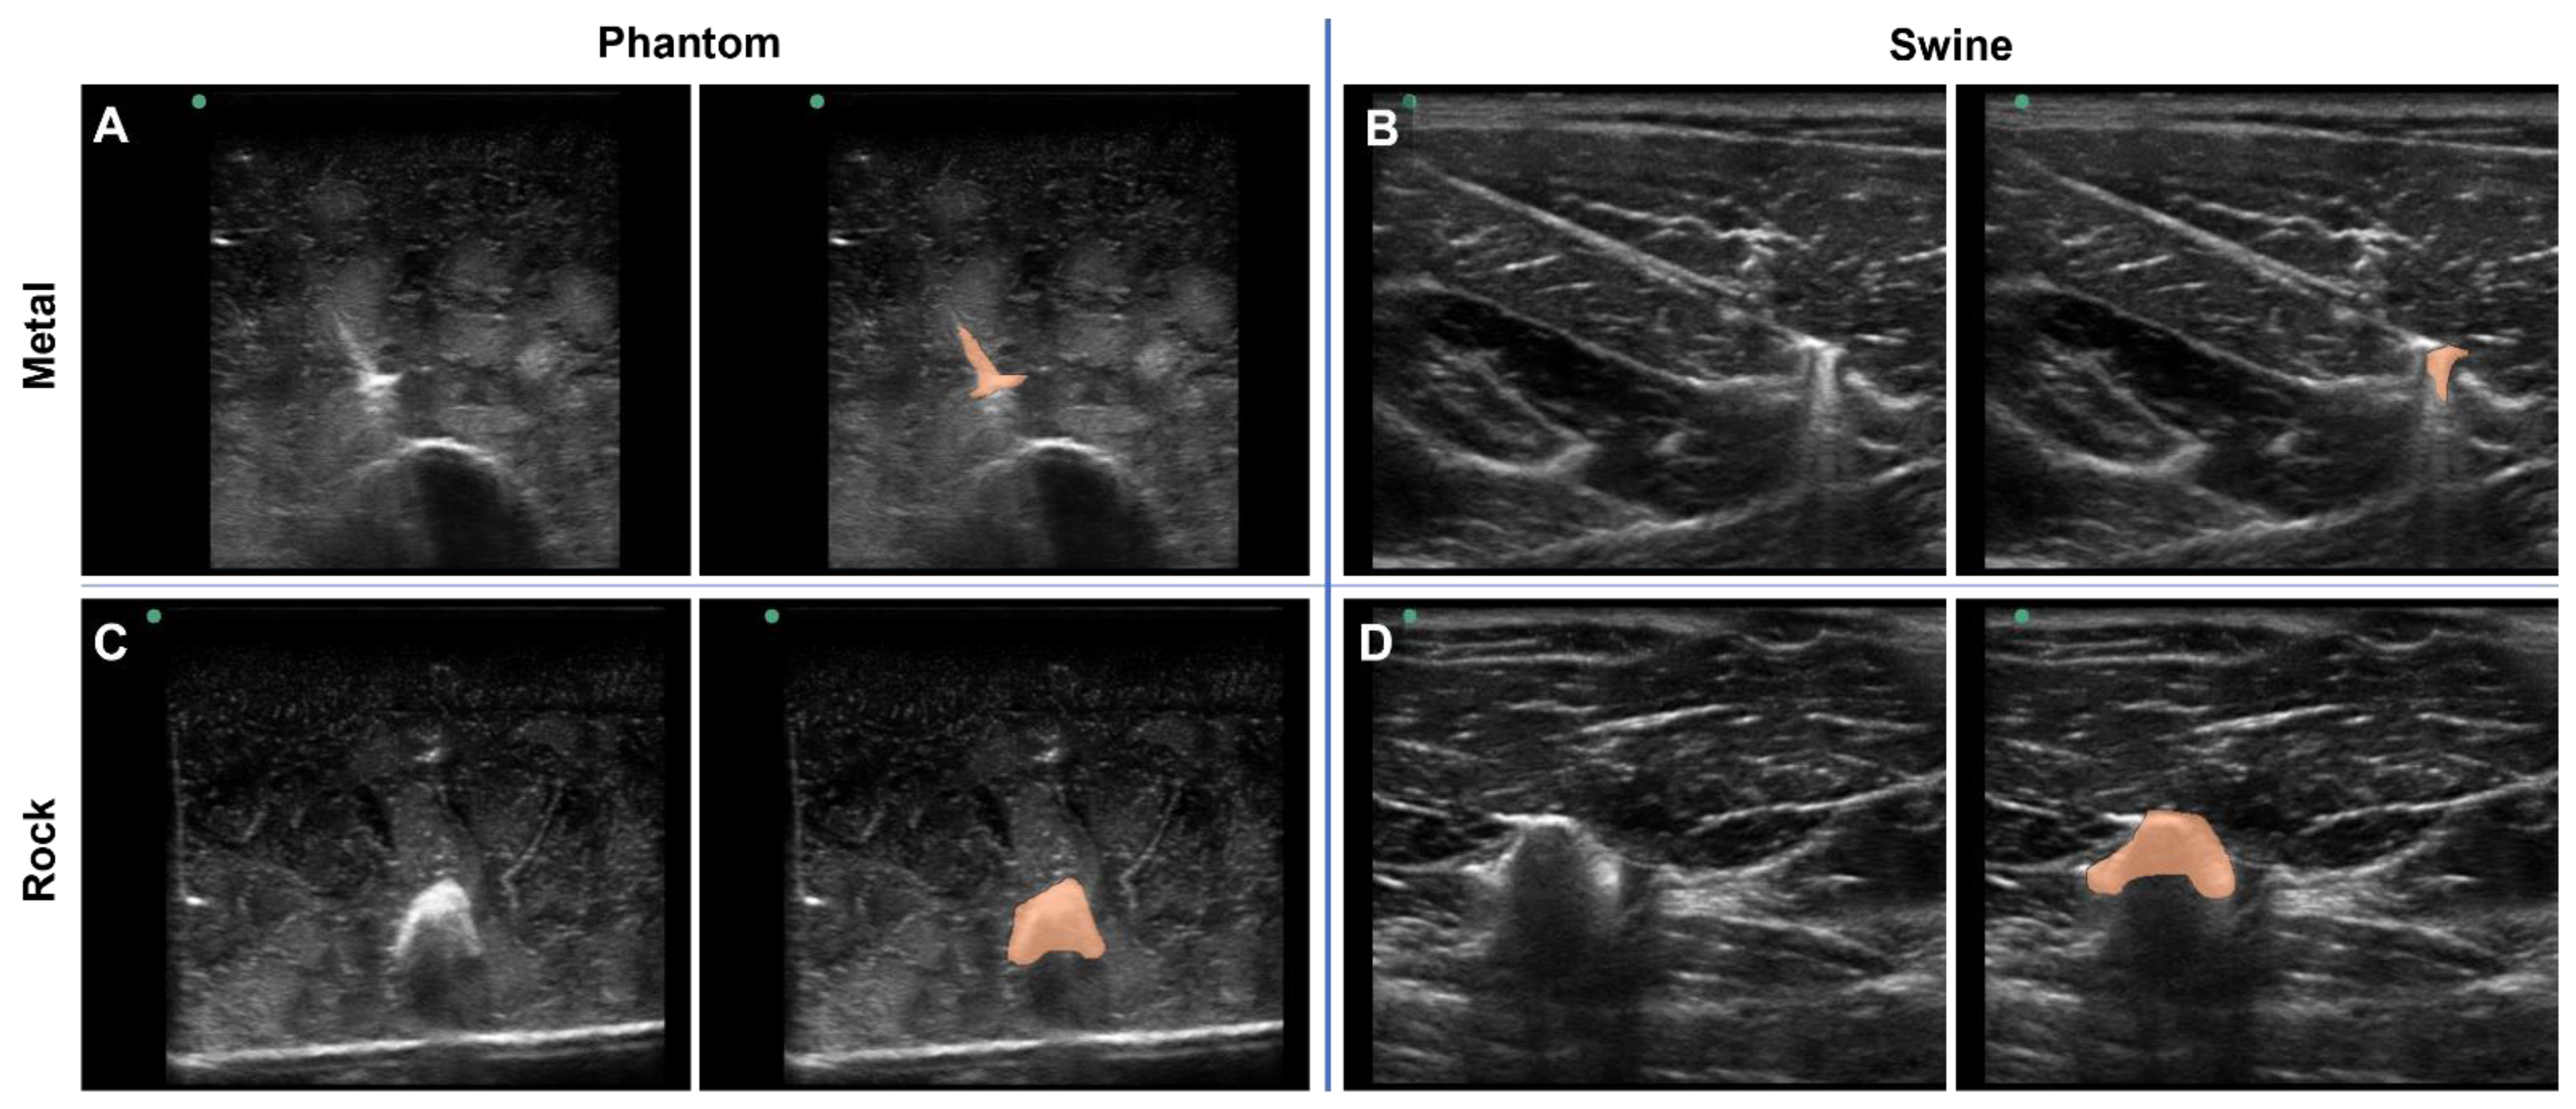

3.1. Overview of the Tissue Phantom for Shrapnel Image Acquisition

3.2. Application for Automated Shrapnel Detection

3.3. Phantom and Swine Training Datasets for ShrapML